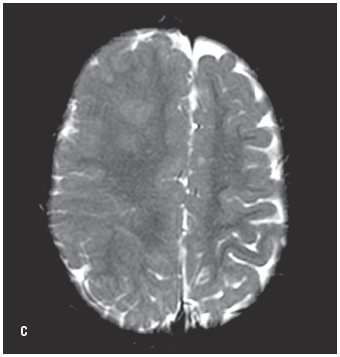

An MRI scan of the brain revealed semilobar holoprosencephaly. Abnormal and incomplete cleavage of the lobes was evident (B, C, and D). The anterior interhemispheric fissure was incompletely visualized on the scan; the posterior interhemispheric fissure was present. There was partial fusion of the basal ganglia and the thalami (E). An H-shaped monoventricle was noted.

Holoprosencephaly is a congenital malformation of the brain that occurs before the 23rd day of gestation.1 According to severity, holoprosencephaly is classified as alobar and semilobar. In semilobar holoprosencephaly, there is variable separation of the cerebral hemispheres, while in alobar there is complete absence of the interhemispheric fissure. Fusion of the deep gray nuclei including the hypothalamus, thalamus, and basal ganglia is noted.